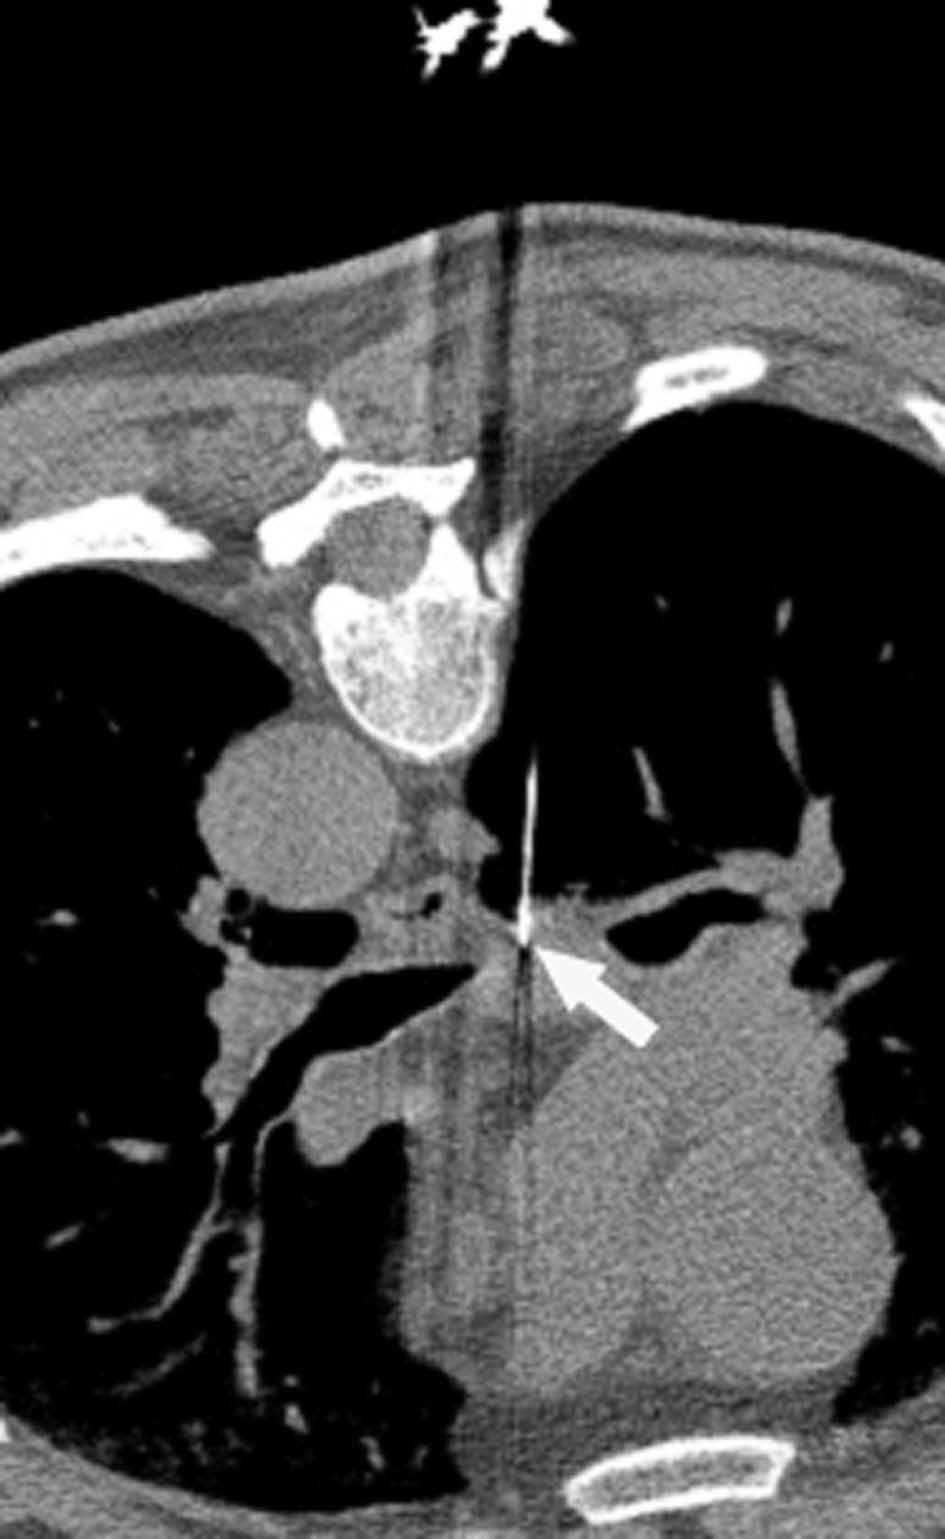

Fig. 2.--T4. (A) Corte axial de tomografía computarizada (TC) torácica con contraste. Tumor hiliar derecho que infiltra la arteria pulmonar derecha, la vena cava superior y engloba al bronquio intermediario. (B) Reconstrucción coronal oblicua, longitudinal al eje de la arteria pulmonar derecha, que muestra cómo engloba el tumor a la rama del truncus superior (flecha blanca) e inferior (flecha negra).